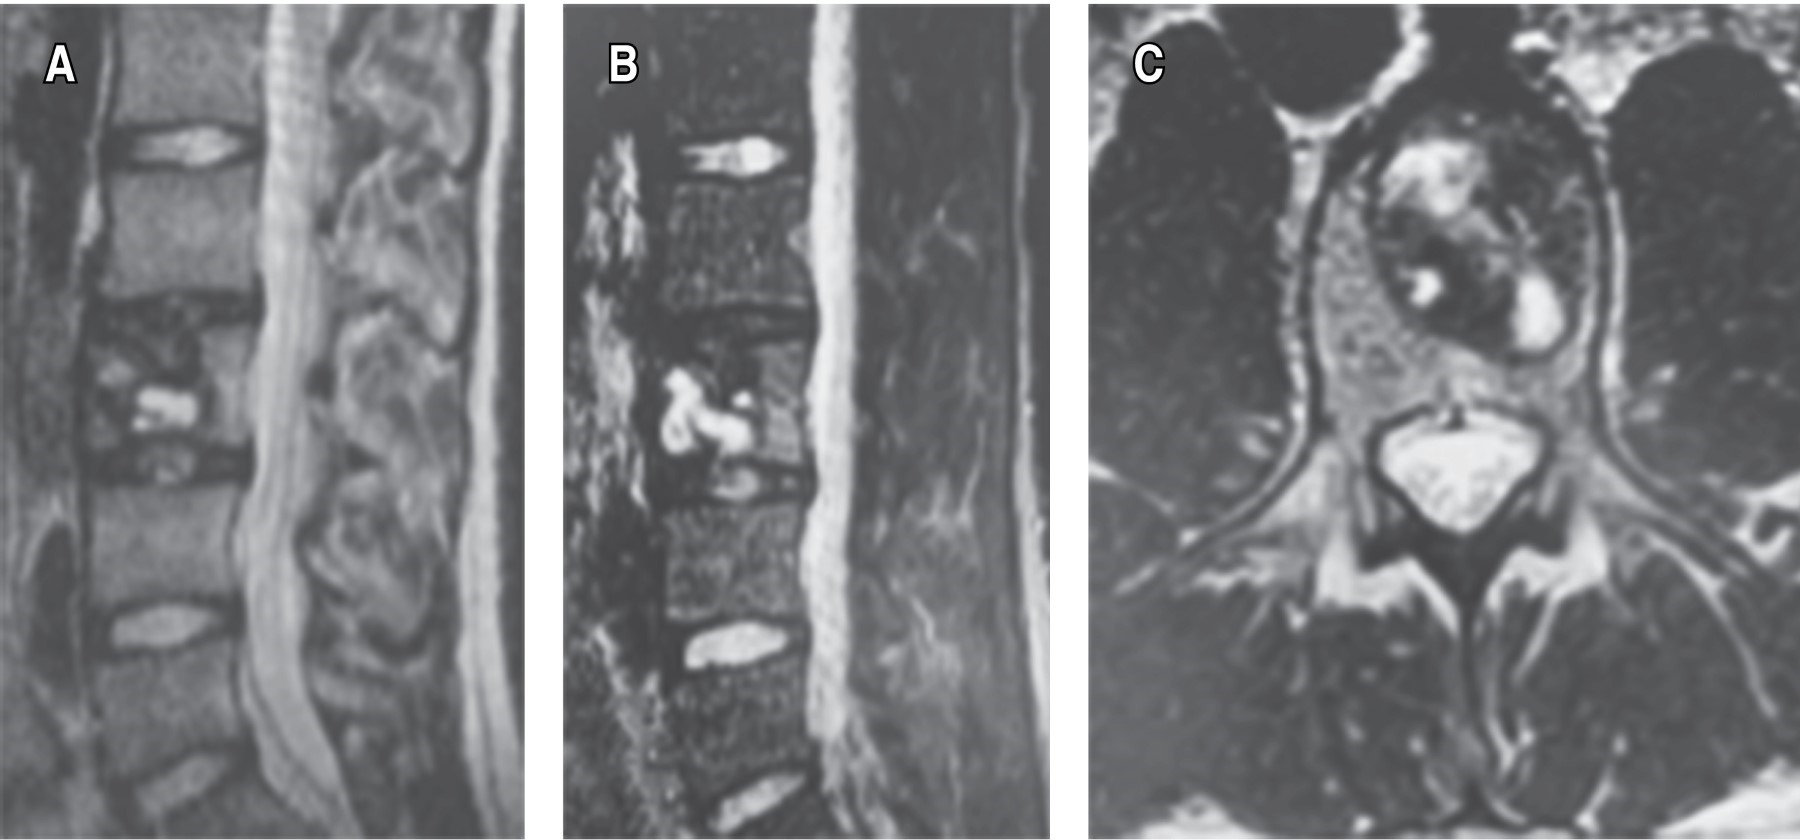

Evolucionando en el postquirúrgico de manera adecuada, se decide su egreso por mejoría clínica, se toman estudios de imagen de control (Figura 3).

El quiste óseo aneurismático de la columna vertebral es una patología benigna que genera destrucción ósea.1 Fue descrito por primera vez por Jaffe y Lichtenstein, en 1942, como una lesión intraósea y osteolítica, diferenciándolo de hemangiomas y otros tumores de células gigantes.2 Suelen crecer rápidamente, con hipervascularidad y proliferación reactiva de tejidos conectivos.3 Representan 1% de los tumores óseos primarios y afectan predominantemente en los primeros 20 años de vida.4,5 Presenta ligero predominio en mujeres. Después del osteoma osteoide y el osteoblastoma, es el tercer tumor óseo benigno más frecuente.6 Es una entidad poco frecuente, caracterizada por una agresiva destrucción ósea que conlleva a deformidad espinal, con significativas manifestaciones clínicas, derivadas del compromiso de estructuras neurales y tejidos blandos.1 Pueden provocar síntomas como dolor de espalda, déficit neurológico y fracturas patológicas.3 El dolor es la queja más común, principalmente en la zona lumbar, por las noches.6 La fisiopatología de los quistes óseos aneurismáticos es cuestión de debate, la mayoría de los autores proponen que se desarrolla como resultado de un edema intercelular causado por la lesión primaria que expande el estroma laxo circundante y permite la ruptura de los vasos hacia los microquistes bajo presión hemodinámica, provocando así un quiste lleno de sangre.4,7 Afectan principalmente a huesos largos, pero hasta 20% ocurre en la columna vertebral, predominantemente en elementos posteriores.4,8,9 La región cervical se ve comprometida en 30-40% de los casos, la columna torácica en 25-50% de los casos, y el segmento lumbar en 40-45%.2,10,11 El diagnóstico definitivo se obtiene a partir de hallazgos radiológicos e histopatológicos. Aparecen como lesiones líticas expansivas con márgenes escleróticos. Histológicamente aparecen como espacios llenos de sangre, separados por tabiques fibrosos, revestidos por fibroblastos e histiocitos, hay células osteoclásticas, sin atipia.4 En la tomografía y en la resonancia se pueden observar los niveles de líquido-líquido, lesiones con múltiples tabiques internos o colapso de cuerpo vertebral.6 Se debe realizar diagnóstico diferencial con el quiste óseo unicameral, tumor de células gigantes, osteosarcoma telangiectásico, condroblastoma y el osteoblastoma.12

La cifoplastía es una opción alternativa de tratamiento quirúrgico seguro y eficaz para el quiste óseo aneurismático, cuando no existen alteraciones estructurales ni inestabilidad de la columna vertebral, teniendo esta técnica un gran potencial para prevenir el colapso vertebral patológico, corrección de la deformidad vertebral secundario a fracturas de origen neoplásico, sumando el alivio rápido del dolor, disminución del tiempo de estancia hospitalaria e integración temprana a las actividades cotidianas del paciente.